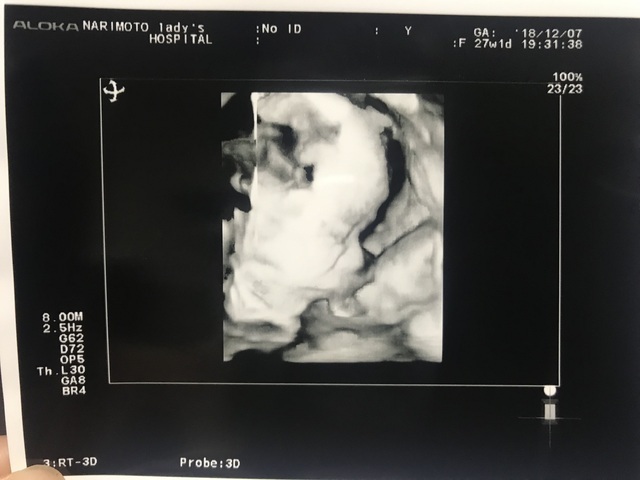

27週1日(27w1d・女の子)|natsu8 さん(27歳)

エコー写真撮影時のエピソード:

妊娠後期に入ってからは、後期つわりがあり、食事が楽しくありませんでした。つらかったです。また、睡眠もまとめてとれなくなり、幸せなマタニティライフではありませんでした。

このエコー写真の時期は、やっと顔を見せてくれるようになり、かわいい顔でうまれてきてくれることを祈っていた記憶があります。